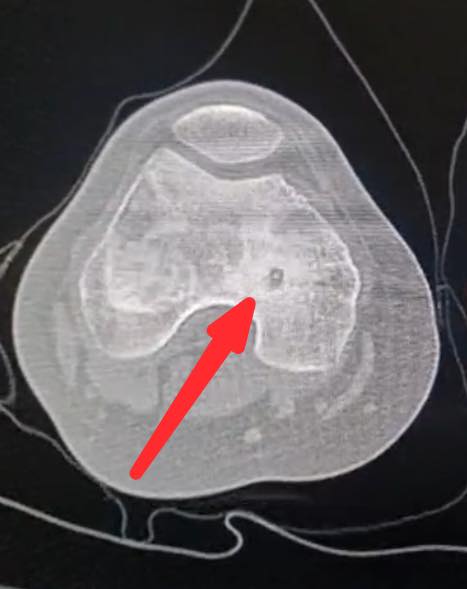

اجرى الكادر الطبي في مستشفى الأميرة بسمة عملية نوعية دقيقة لعلاج ورم عظمي حميد من نوع (Osteoid Osteoma) باستخدام تقنية الكي بالتردد الحراري (Radiofrequency Ablation) الموجهة بالأشعة المقطعية.

وبين الفريق الطبي أن خصوصية هذه الحالة تكمن في عمر المريضة (14 عاماً) حيث استقر الورم مباشرة على صفيحة النمو (Growth Plate) في عظم الفخذ البعيد. وتعتبر هذه المنطقة من الحساسية بمكان إذ ان أي خطأ قد يؤثر على النمو المستقبلي للعظم ما جعل استخدام تقنية الكي الحراري تحديا كبيرا يتطلب دقة فائقة لتجنب إلحاق أي ضرر حراري بالأنسجة المحيطة.